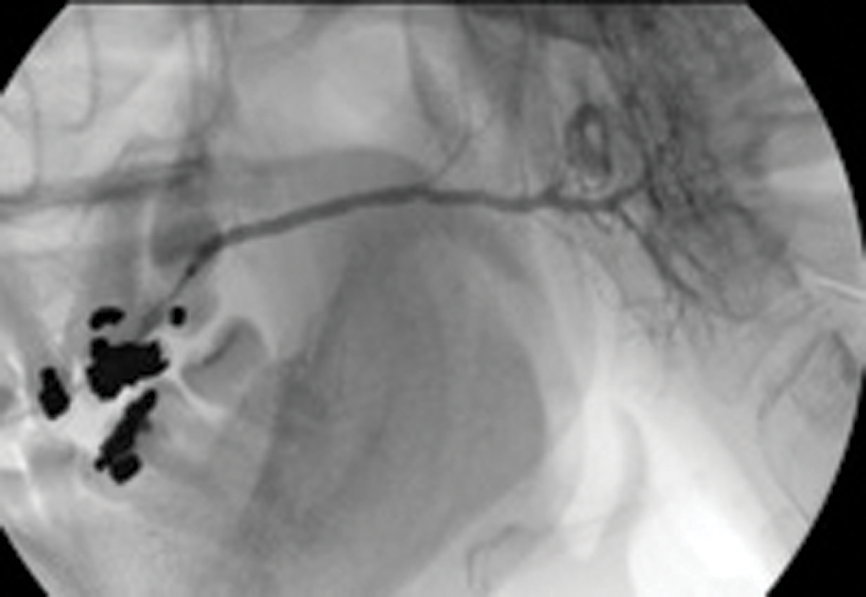

Figure 4: (A) Sialogram showing multiple stenoses located in the parotid duct before treatment.

Figure 4: (B) Appearance on sialogram following balloon dilatation.

Treatment of salivary duct stenosis by interventional sialography

Salivary duct stenosis is a surprisingly frequent phenomenon, being the prime cause in 24% of all cases of benign salivary gland obstruction in a study by Ngu. Strictures of 75% were found in the parotid ducts, and women were affected in 72% of cases [2]. This represents a substantial body of symptomatic individuals who may seek symptomic relief but who frequently do not feel that a surgical solution, such as superficial parotidectomy, with its attendant risks and complications, is justified.

Ductoplasty involves insertion of a fine angioplasty balloon using an on-the-wire-technique into the salivary duct, and manipulation of the balloon catheter through the duct stenosis. Again this is performed under radiological guidance and local anaesthesia. The balloon is inflated, the dilatation being maintained or repeated to eliminate any waisting in the balloon.

Our study has shown a 92% success rate in achieving balloon dilatation, with 82% demonstrating complete elimination of the stricture postoperatively [13].